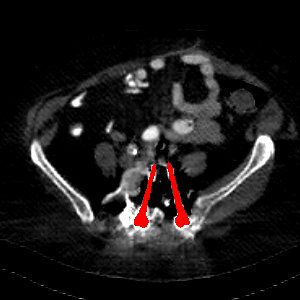

Visual comparison. As shown in Fig. 5, metallic implants such as spinal rods and hip prosthesis cause severe streaky artifacts and metal shadows, which obscure bone structures around them. cGan-CT cannot recover image intensity correctly for both cases. Sinogram domain or dual-domain methods perform much better than cGan-CT. LI, NMAR, and CNNMAR introduce strong secondary artifacts and distort the whole images. In NMAR images, there are fake bone structures around the metals, which is related to segmentation error in the prior image from strong metal artifacts. The segmentation error is also visible in NMAR sinogram. CNNMAR cannot restore the correct bone structures between rods in case 1. The tissues around the metals are over-smoothed in DuDoNet because LI sinogram and image are used as inputs, and the missing information cannot be inferred later. Our model retains more structural information than DuDoNet and generates anatomically more faithful artifact-reduced images.

Visual comparison. Fig. 7 shows two clinical CT images with metal artifacts. Case 1 is with moderate metal artifacts. cGan-CT does not suppress the artifacts completely and generates some fake details. LI, NMAR, CNN-MAR remove all the artifacts but introduce new streak artifacts, which is caused by the discontinuity in the corrected sinogram. DuDoNet outputs over-smoothed sinogram, which leads to blurred tissues close to the metal implants, such as muscle and bone. Only our model can provide realistic enhanced sinogram and remove the artifacts while retaining the structure of nearby tissues. Case 2 is very challenging as the rods bring strong metal shadows and bright artifacts around the vertebra. cGan-CT recovers the shape of vertebra but changes the overall image intensity. Other sinogram inpainting methods fail as the soft tissue and bone near the rods are heavily distorted. Our model removes part of the dark bands and reproduces correct anatomical structures around the rods.